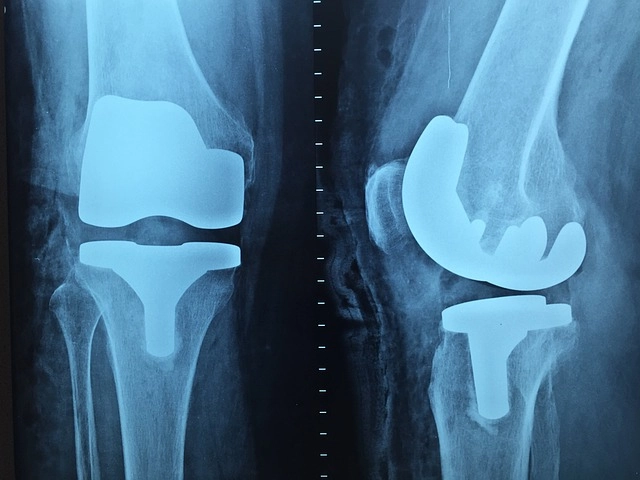

Д-р Точков извършва диагностика, лечение и операции на опорно-двигателния апарат. Специалист е в областта на артроскопската хирургия, в частност хирургия на колянната става (увреди на менискусите, коленните връзки, ставния хрущял и др.) и спортната травматология.